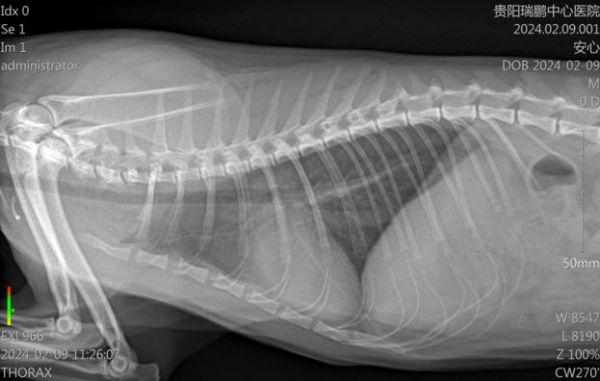

以下为外院提供的X线片,从X线片可见胸腔整体不投射性增加,心影轮廓不清,心脏增大,正位心脏呈”情人心“;肺前动静脉扩张,前腹侧和后腹侧可见混合肺泡型,怀疑肺炎、肺水肿、肺出血等;心脏略增大、心尖钝圆,需结合超声心动图诊断。

4.2.5 胸腔X线光(2.09)

结果提示:X线片可见肺水肿已经明显改善。